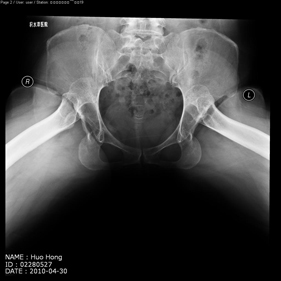

- total hip replacement on hips with u…

shortening osteotomy and total hip replacement for bilateral severe dysplasia of hip with high riding